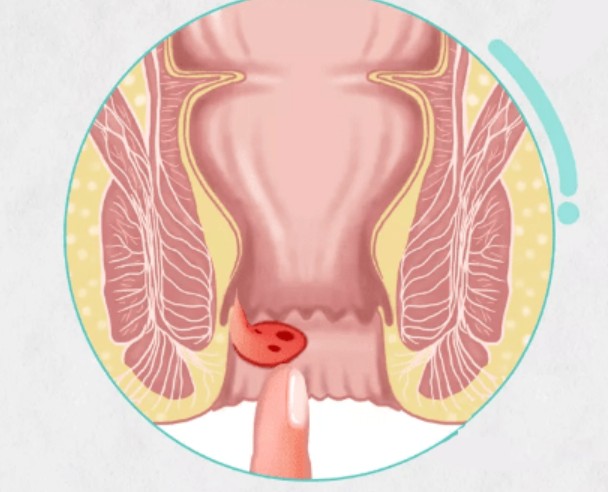

外痔圖片

血栓性外痔

血栓性外痔

血栓性外痔